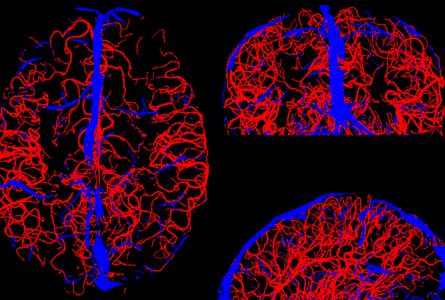

The vasculature of the cerebral cortex orchestrates the allocation of energy resources, oxygen and glucose, throughout cortical areas with different levels of activity and computational complexity. Furthermore, active neurons affect vasodynamics through the process of neurovascular coupling. This allows functional magnetic resonance imaging (fMRI) to infer neuronal processing in humans from changes in blood flow and oxygenation.

We seek to understand how brain-wide neuromodulatory (cholinergic, dopaminergic, etc.) neuronal circuits participate in control of large-scale vasodynamics patterns observed in fMRI experiments in order to infer features of the underlying brain state dynamics from fMRI data.

Ultra-high-resolution in vivo imaging of cerebral vasculature in humans

Jon Polimeni and his team have obtained unprecedented images of the pial arterial vasculature of the human brain in vivo Read more